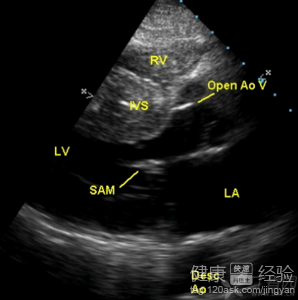

我母親今年已經有六十二歲了,大概在早二十年的時候,我母親就患有了高血壓的病症,而今天到醫院復查,檢查結果顯示升主動脈3.3cm,左心房3.8cm右室內徑2.0cm,右心房3.0cm,主肺動脈1.8cm,時間隔基底厚1.6cm最後處1.8cm,左室厚壁1.5cmlvef:58%,lvfs:30%,醫生根據我母親的體檢報告,說我母親患有了非對稱性肥厚性梗阻性心肌病,那到底這應該要怎麼辦啊?